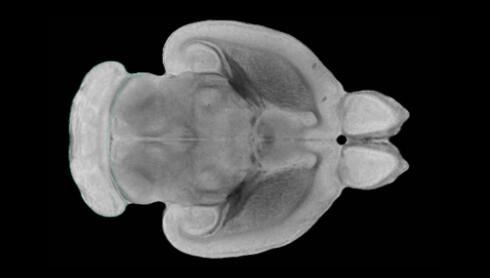

隨著機(jī)體年齡增加,肌肉和關(guān)節(jié)都會(huì)變得僵硬,這就會(huì)使得日?;顒?dòng)變得更加困難,本文研究表明,我們的大腦也是如此,與年齡相關(guān)的大腦僵硬對大腦干細(xì)胞的功能或許有著重要影響。文章中,研究人員對年輕和老化大鼠的大腦進(jìn)行研究闡明了年齡相關(guān)大腦僵硬對少突膠質(zhì)前體細(xì)胞(OPCs,oligodendrocyte progenitor cells)功能的影響。OPCs是一類對維持正常大腦功能非常重要的大腦干細(xì)胞,其對于髓磷脂的再生也非常重要,髓磷脂是神經(jīng)組織周圍的脂肪鞘,在多發(fā)性硬化癥中髓磷脂的再生常常會(huì)被損傷,機(jī)體老化對這些細(xì)胞的影響常常會(huì)誘發(fā)多發(fā)性硬化癥的發(fā)生,這些細(xì)胞的功能在老化的健康人群中同樣會(huì)下降。

為了確定老化OPCs的功能缺失是否可以被逆轉(zhuǎn),研究人員將來自老化大鼠機(jī)體的老化OPCs轉(zhuǎn)移到了年輕大鼠柔軟的海綿狀大腦組織中去,值得注意的是,這些老化的大腦細(xì)胞能夠重新恢復(fù)活力,其行為非常像年輕更加強(qiáng)壯的細(xì)胞。這項(xiàng)研究中,研究人員在實(shí)驗(yàn)室中開發(fā)出了具有可變僵硬程度的新型材料,并在受控環(huán)境下研究這些材料的生長及其對大鼠大腦干細(xì)胞的影響,這些材料能被工程化改造具有和年齡或老化大腦相似的柔軟程度。